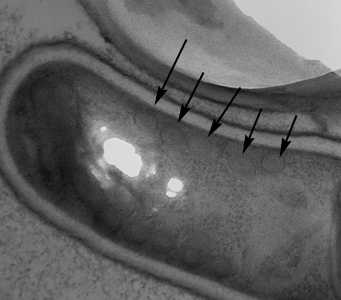

This was a case of microsporidiosis caused by Encephalitozoon intestinalis. Figures A-D showed vacuolated spores that were positive by both the Gram chromotrope and chromotrope 2R stains. Additionally, molecular testing and electron microscopy (EM) were performed on the BAL specimen by the DPDx Team and the CDC’s Infectious Diseases Pathology Branch, respectively. The EM demonstrated that the spores contained roughly 5 coils of the polar tubule (arrows, Figure E), which is suggestive of Encephalitozoon in combination with a size of roughly 2.0 micrometers. Molecular testing, including both a nested PCR test and sequencing analysis, confirmed the species as E. intestinalis. Interestingly, microsporidia were not observed in other clinical specimens.

Figure E